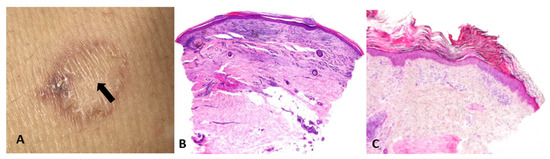

- Presentation: Rapidly enlarging ulcer with undermined violaceous borders and severe pain (Figure 9A).

Figure 9. Ulcerative cutaneous leishmaniasis misinterpreted as pyoderma gangrenosum. (A) A large cutaneous ulcer with a bleeding, fibrinoid bed and an irregular, violaceous, undermined border. (B) High magnification demonstrating Leishmania amastigotes within macrophages. - Abductive step: Pyoderma gangrenosum (PG) is high on the list.

- Deduction: Expect sterile neutrophilic dermal infiltrates; history of IBD or arthritis; paradoxical worsening with surgical debridement; response to steroids.

- Test: Biopsy shows neutrophilic and granulomatous infiltrate (Figure 9B), but treatment fails. Travel history reveals exposure risk. Re-evaluation of sections at high power and Giemsa stain identifies intracellular parasites; PCR confirms Leishmania.

- Update: New abductive hypothesis—cutaneous leishmaniasis—supersedes PG; itraconazole leads to cure.

- Lesson: Nonmonotonicity is not diagnostic failure; it is diagnostic hygiene. Therapy response is itself a test within the ST-Model.